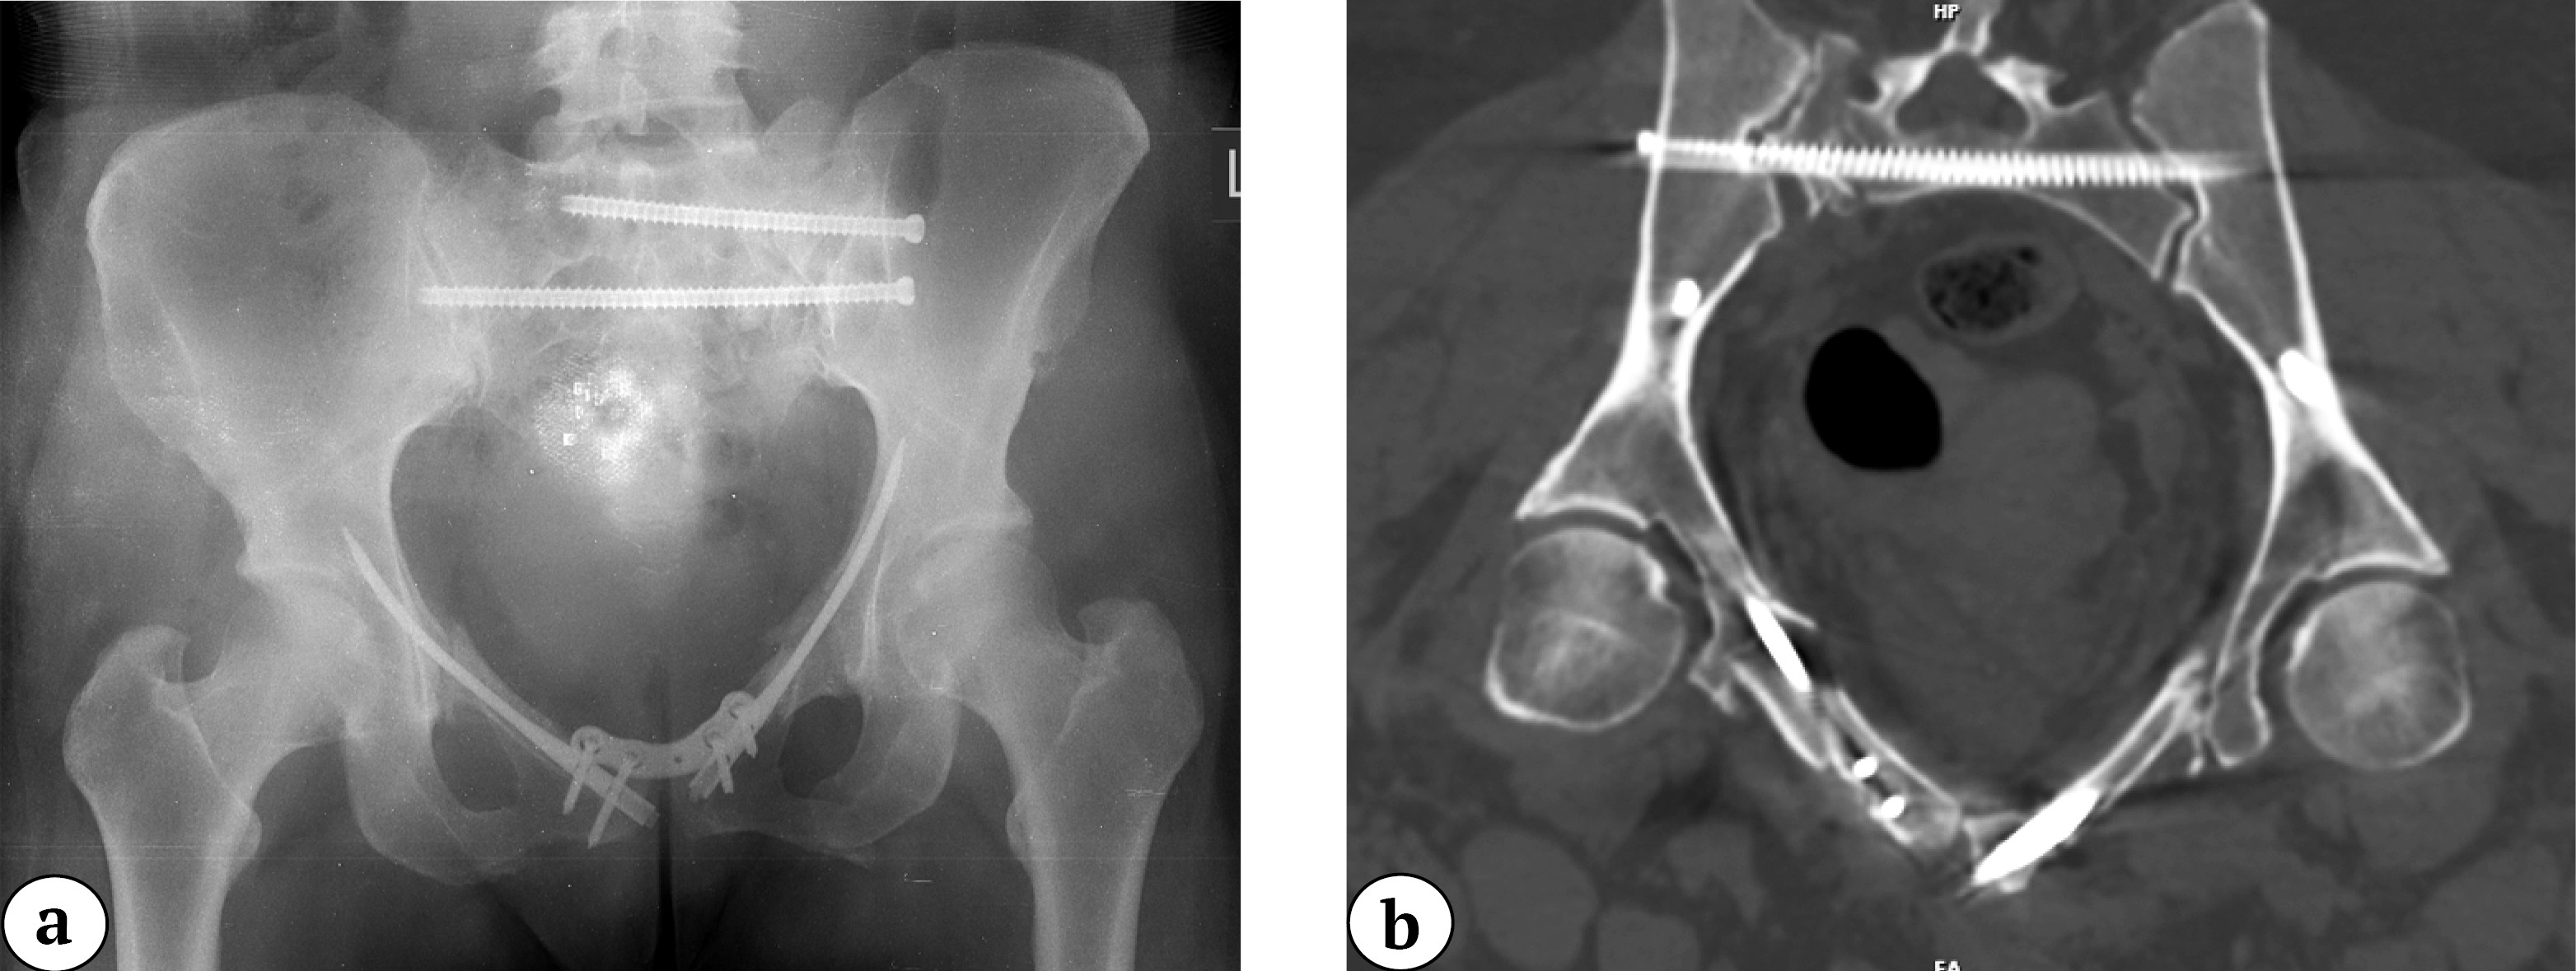

It is important to note that the presented method of anterior pelvic ring stabilization is usually part of a comprehensive surgical approach. In cases associated with posterior ring instability, it should be combined with appropriate fixation techniques, chosen indi-vidually based on the complete diagnostic assessment. In our practice, cannulated 6.5-mm screws were typically used (Figure 8).

Figure 8. Postoperative X-ray: anterior fixation with the nail-plate system and sacral fixation with cannulated screws in S1 and S2 (a); 2D CT reconstruction of the pelvis postoperatively confirming restoration of the pelvic ring anatomy with fixation of the sacrum, pubic bones, and symphysis (b)